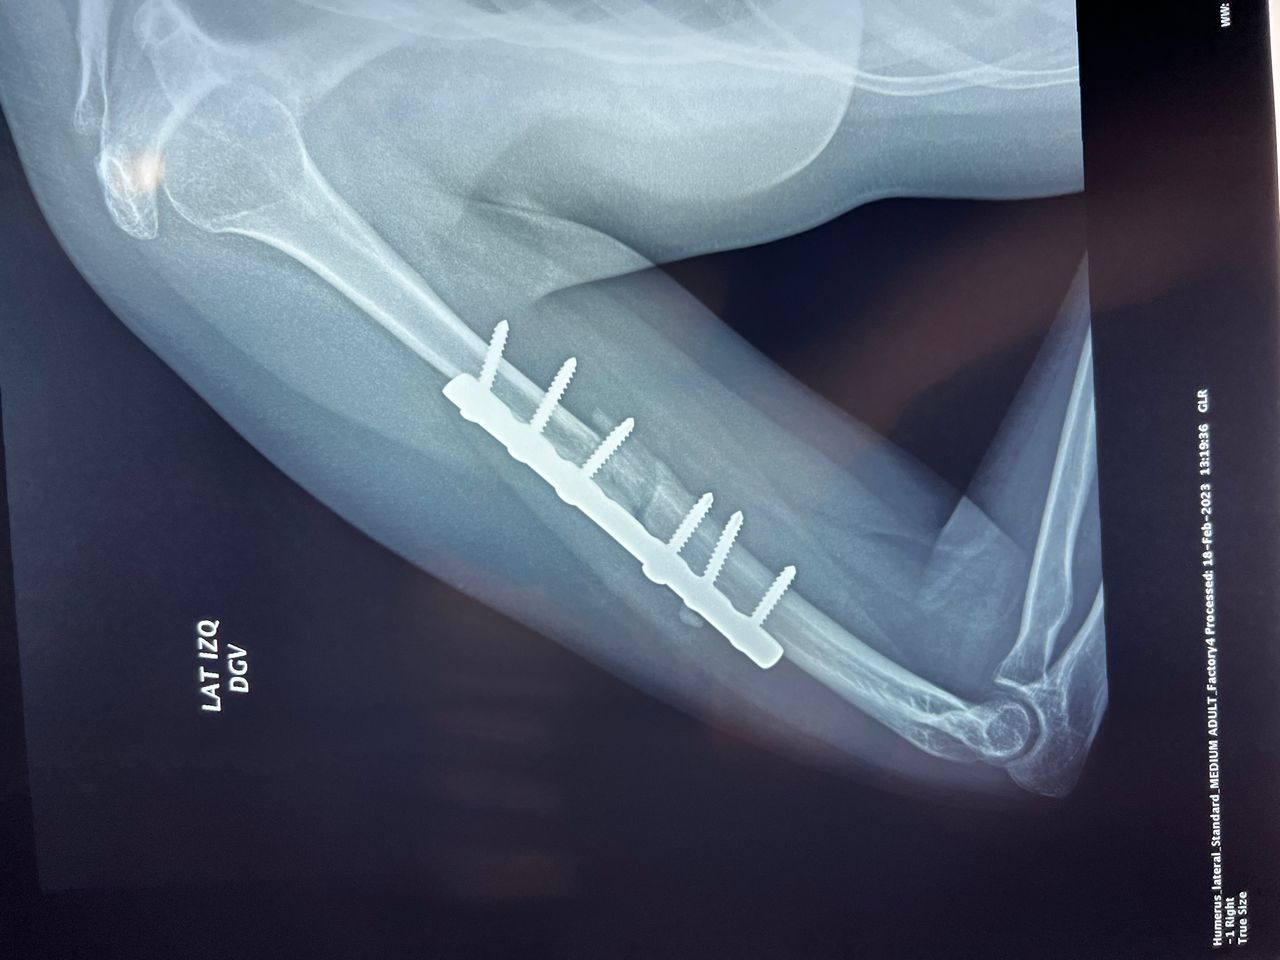

Fotos y videos

El doctor tiene mucha experiencia, muy buena atención y la ayuda de la toma de placas excelente.